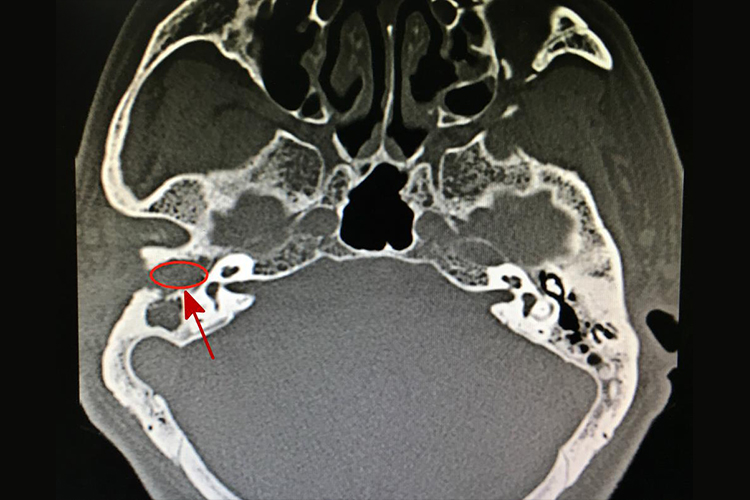

胆脂瘤CT主要表现为上鼓室、乳突窦口及乳突窦内边缘光滑、膨胀性的软组织等密度或低密度团块影。听小骨破坏、移位,使部分或全部岩骨尖扩大成一空腔状。岩尖骨质破坏边缘整齐、有硬化。病灶增大时,骨迷路、内耳道、颈动脉管及面神经管等均可能受累,出现传导性耳聋等症状。